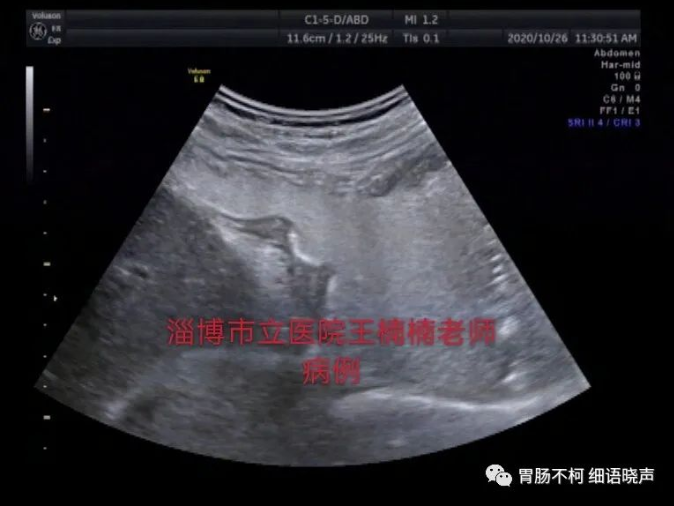

但在应用的时候,应注意不典型病例带来的鉴别困扰。比如胃壁因炎症水肿增厚明显,易导致良性溃疡与“土堆挖坑征”不易鉴别;浸润溃疡型胃癌的溃疡,易表现为“平地挖坑征”;愈合期溃疡与浸润溃疡型胃癌的鉴别有困难。无论典型不典型,抓住细节特征,最终将其鉴别开来。思考一下:以下几个溃疡,其良恶性鉴别点在哪里?